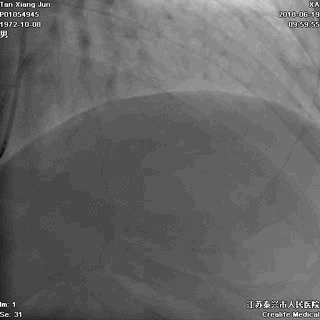

广东佛山有位姓谭的男子,年仅45岁,只身一人出差来江苏泰兴,突发胸痛,9小时后就诊于江苏省泰兴市人民医院,心电图诊断为“急性心肌梗死”。

他在这里举目无亲,该怎么办?

听了医生的建议后,他当机立断,自己签字接受急诊手术。这是一个大胆而又明智的决定!医生立即为谭某进行了介入手术,打开了闭塞的血管,恢复了心肌的血液供应。

闭塞的前降支血管开通了,心肌的血供恢复了

记住:出门在外发生“急性心梗”,如果身边没有亲人,能够救你一命的只有医生!请相信他,果断签字手术。不要等待配偶,不要等孩子,更不要犯傻地要求回当地手术。命运此刻就掌握在你自己手中。